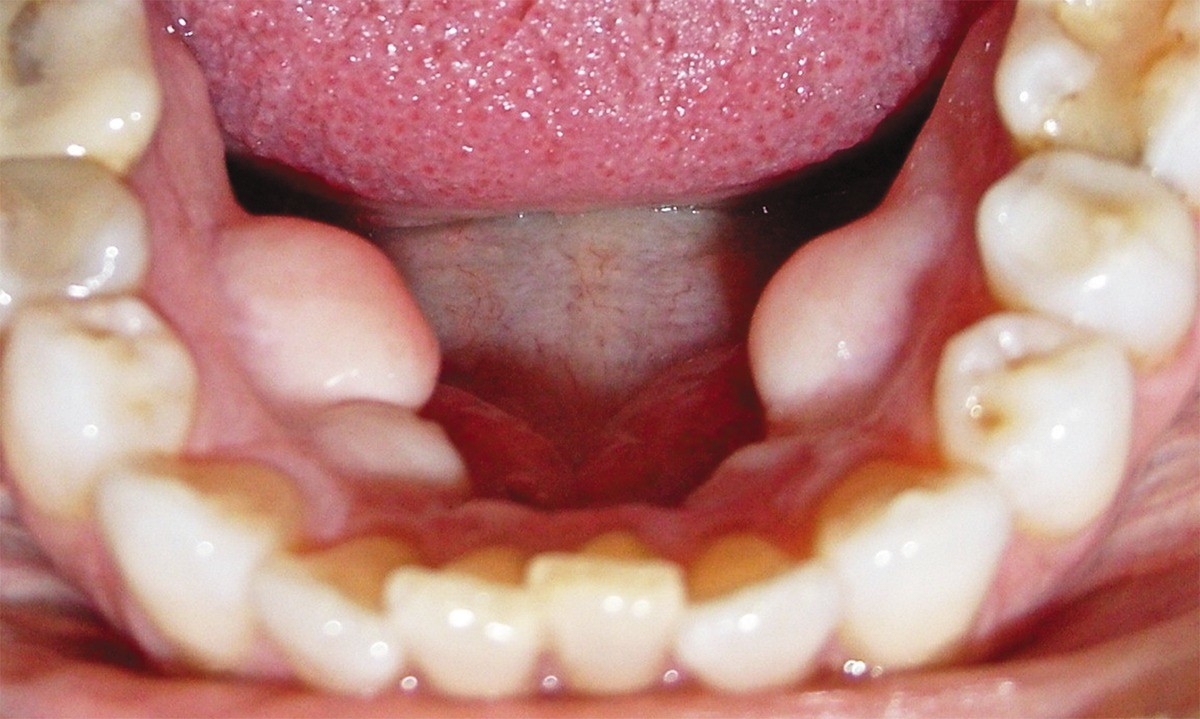

Torus mandibularis is a bony growth that develops on the lower jaw, beneath and on the side of the tongue. Tori affects about 27 out of every 1,000 adults, reports the National Institutes of Health (NIH), though it's not as well-known as other oral health conditions. Here are four things you need to know about this uncommon condition.

This condition presents as a bony growth beneath and on the side of the tongue. You may have one growth or multiple growths, and they can develop on one side of your mouth or on both sides. While it's usually asymptomatic, this condition can sometimes cause problems. If you wear dentures, the growth can interfere with the fit of your lower denture. Your denture may be uncomfortable and may not stay in place. The soft tissues that cover the growth can also become ulcerated in some cases.